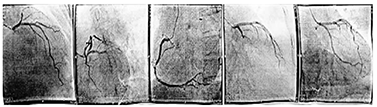

患者 男,43岁,因"反复胸前区疼痛约10 h,加重约3 h"入院。患者2014年2月5日早晨8: 00左右无明显诱因突然出现胸前区、上腹部阵发性疼痛,疼痛位置不固定,向背部放射,伴有胸闷,症状数分钟后能自行缓解,但症状反复发作,当日13: 00来我院诊治,14: 05查丙氨酸氨基转移酶(ALT) 25 U/L(正常值9~ 52 U/L)、天冬氨酸氨基转移酶(AST) 33 U/L(正常值15~ 46 U/L )、乳酸脱氢酶(LDH) 442 U/L(正常值313~ 618 U/L)、肌酸激酶(CK) 71 U/L(正常值30~ 170 U/L )、肌酸激酶同工酶(CK-MB) 20 U/L(正常值0~ 16 U/L)。患者14: 27胸痛间歇期查十二导联心电图示下侧壁导联ST段改变(图1),后患者疼痛有所好转,拟诊腹痛待查,不排除冠心病、心绞痛,给予麝香保心丸后患者离院。15: 00左右患者疼痛加重,剑突下疼痛明显,症状持续不缓解,阵发性加剧,伴有恶心、呕吐、出汗,无晕厥、心悸、呼吸困难,收入院进一步诊治。患者平素吸烟,每天约吸1包烟,否认高血压、糖尿病病史。查体:血压154/109 mmHg (1 mmHg= 0.133 kPa),两肺未闻及干、湿性啰音,心率92次/min,律齐,无杂音,腹平软,上腹部轻压痛,无反跳痛,未触及包块,肝脾肋缘下未触及,Murphy征阴性,肝肾区无叩击痛,双下肢无水肿。胸部X线片无异常。18: 25十二导联心电图无异常(图2)。18: 26查ALT 28 U/L、AST 19 U/L、LDH 433 U/L、CK 83 U/L、CK-MB 16 U/L,血糖、肾功能、血淀粉酶、凝血功能无异常。给予吸氧、严密监护、抗血小板聚集、扩张冠状动脉等处理。胸部、腹部增强CT未见胸腹部异常情况,无主动脉夹层形成。患者症状缓解不明显。22: 30查ALT 27 U/L、AST 36 U/L、LDH 431 U/L、CK 289 U/L、CK-MB 58 U/L,肌钙蛋白T 253 ng/L,血淀粉酶正常。次日0: 10十八导联心电图正常(图3, 图4)。诊断为冠心病、急性心肌梗死、心功能Killip 1级,行冠状动脉造影检查:左前降支近中段狭窄30%,对角支无狭窄;左主干无狭窄;右冠状动脉无狭窄,左回旋支近段完全闭塞;各血管间未见明显的侧支循环(图5)。手术中发现左回旋支近段严重固定狭窄并急性闭塞,予回旋支植入2枚药物支架。数天后患者病情好转出院。